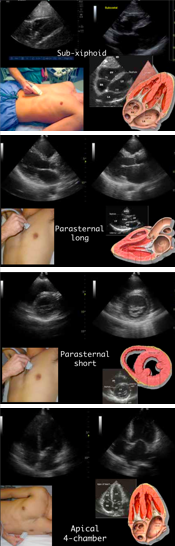

Assessing the pump

1) Contractility (ejection fraction) 2) Effusion 3) RV strain. Assess w/parasternal views (long and short), subxiphoid and apical views.